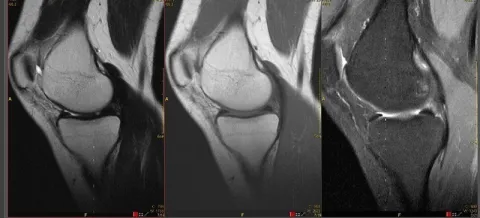

Комплексное МРТ суставов в Тушино представляет собой современный метод диагностики, позволяющий получить детализированные изображения внутренних структур суставов. Этот вид исследования часто рекомендован для выявления различных заболеваний и травм, таких как артрит, бурсит, травмы связок и хрящей. МРТ является одним из наиболее информативных способов визуализации, что делает его важным инструментом в ортопедии и травматологии.

Комплексное МРТ суставов в Москве представляет собой один из наилучших способов исследования анатомического строения и состояния структур, связанных с суставами. Особенность данного метода заключается во взируализации подробнейших деталей внутреннего устройства суставов, включая связочный аппарат, сухожилия, хрящевые ткани, жировую массу, костный мозг и сосудистую систему. Комплексное магнитно-резонансное сканирование суставов позволяет увидеть эти ткани в разных проекциях с необходимым увеличением для высокоточного выявления болезней и анализа развития патологий во времени.